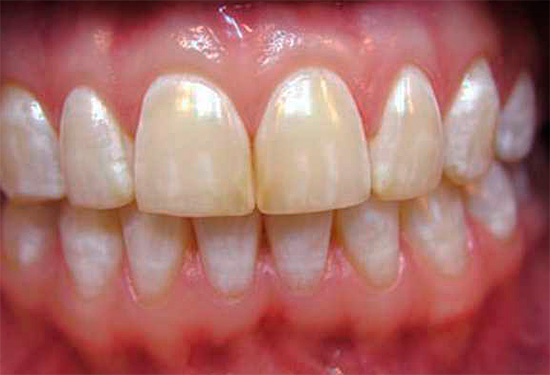

Abaixo estão algumas fotos com exemplos de cárie cervical:

Muitas pessoas começam a levar a cárie cervical a sério e as razões que a causam somente quando o problema é claramente evidente no reflexo no espelho e causa inconvenientes estéticos naturais. A zona de sorriso para pessoas que precisam de comunicação para implementar determinadas tarefas é de particular valor. E como a cárie cervical geralmente é localizada precisamente nos dentes da frente, há uma necessidade urgente de devolver o componente estético.

A foto abaixo mostra um exemplo típico de cárie cervical nos dentes da frente: